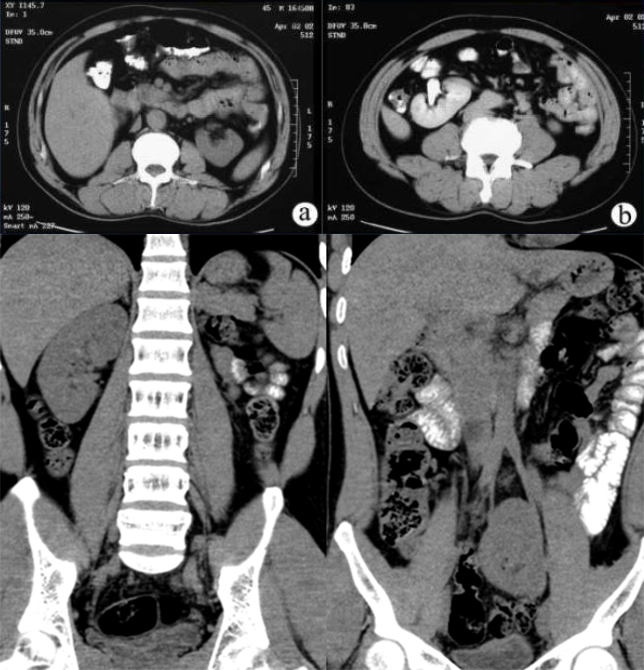

马蹄肾: 是融合肾中最常见的一种, 指两肾的上极或下极相融合,常见下极融合,融合的部分称峡部,由肾实质或结缔组织构成

IVP:两肾下极斜向内侧;两肾盂位置低,且靠近,旋转不良。可伴有肾盂积水